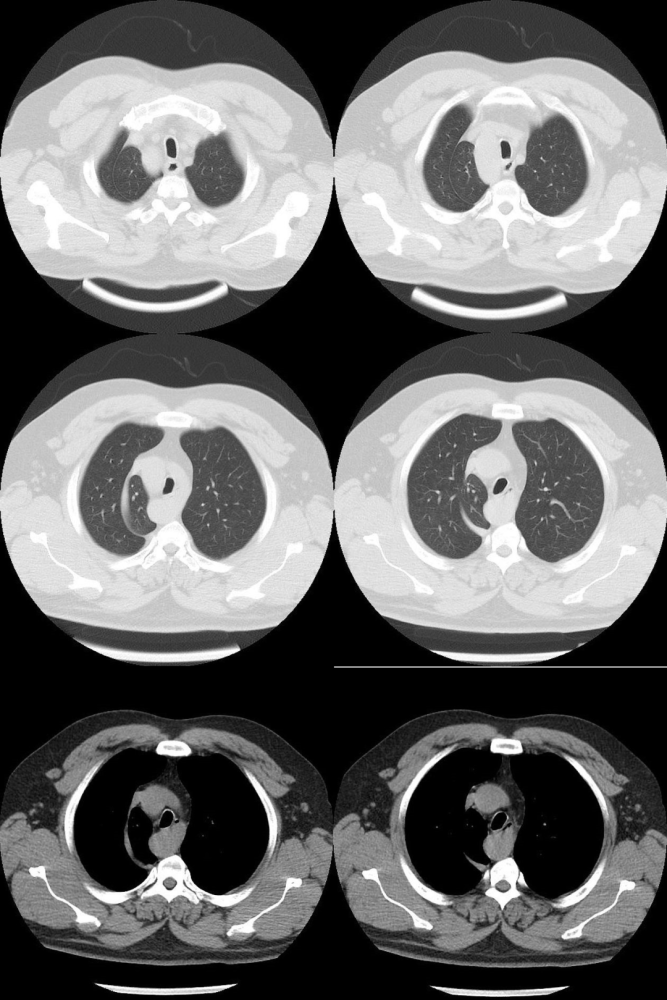

一网打尽肺叶间附属裂

多出来的肺裂,你认识几个?

多出来的肺裂你认识几个